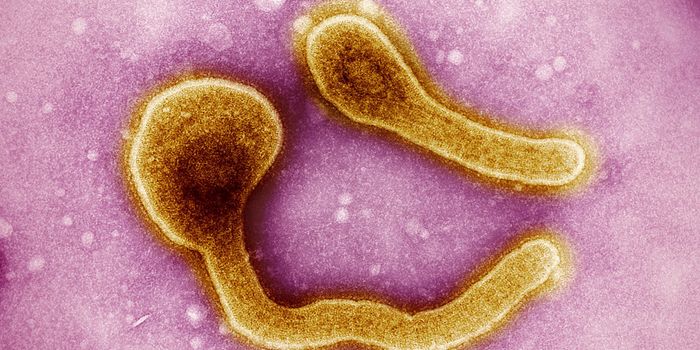

MAR 26, 2023MicrobiologyAn outbreak of Marburg virus began last month in Equatorial Guinea, and more cases have been reported since the outbreak ...

FEB 13, 2023MicrobiologyAn outbreak of Marburg virus has killed nine people and sickened at least sixteen others in Equatorial Guinea's firs ...